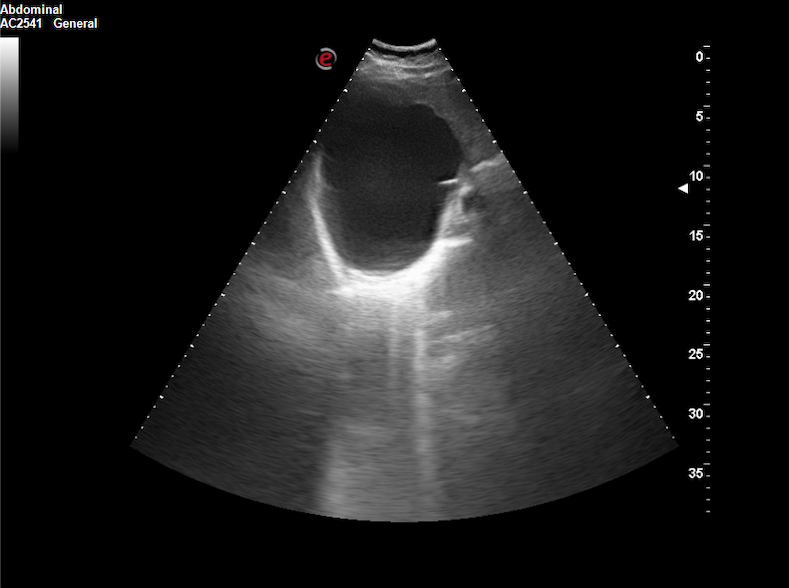

Realizamos ecografía clínica (EC) en nuestro centro de salud, objetivando un quiste de 15 x 12 x 12 cm a expensas de lóbulo hepático derecho, con paredes lisas, refuerzo posterior, contenido anecoico y Doppler-negativo.

La sospecha diagnóstica principal fue de quiste hepático simple.